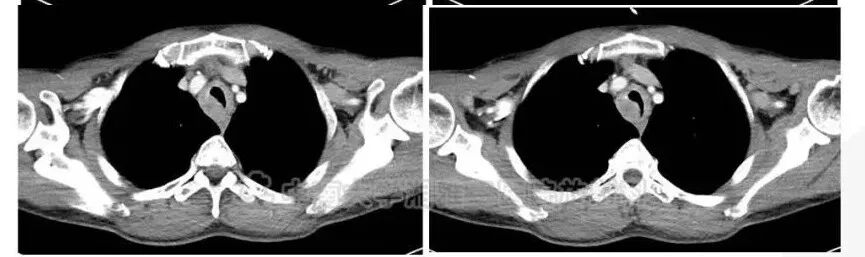

3/18:左主支气管壁弥漫增厚

支气管壁弥漫增厚

腔狭窄,部分堵塞(考虑吸气应该还有间隙)

左侧支气管壁弥漫增厚,腔狭窄,但是未见明显肿块